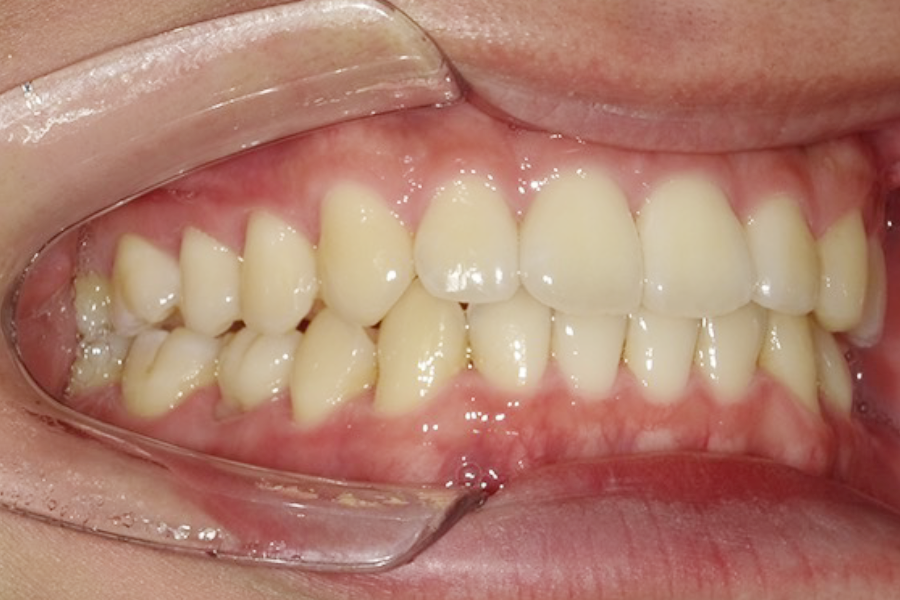

| 主訴 | 歯の重なりを治したい |

|---|---|

| 診断名 | 叢生 |

| 年齢 | 23歳 |

| 治療期間 | 2年 |

| 治療費 | 基本料金 ¥880,000 調整料 ¥5,500/月 |

| 治療内容 | 上下顎左右側第一小臼歯抜歯 マルチブラケット装置(表側) |

| 治療のリスク | 装置の見た目、歯ブラシが難しい、疼痛、口内炎、歯肉退縮、歯根吸収 |